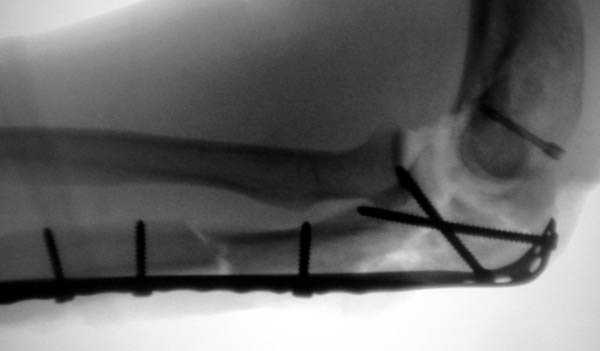

Здесь выставлены несколько случаев и варианты фиксации локтевого отростка, некоторые в комбинации с другими переломами.

1 вариант применен ACUMED локинг пластина

2 вариант

перелом локтевого отростка с переломом головки лучевой кости (использованы 2 мм шурупы)

3 вариант

перелом с capitelum humerus и проксимальной трети улна